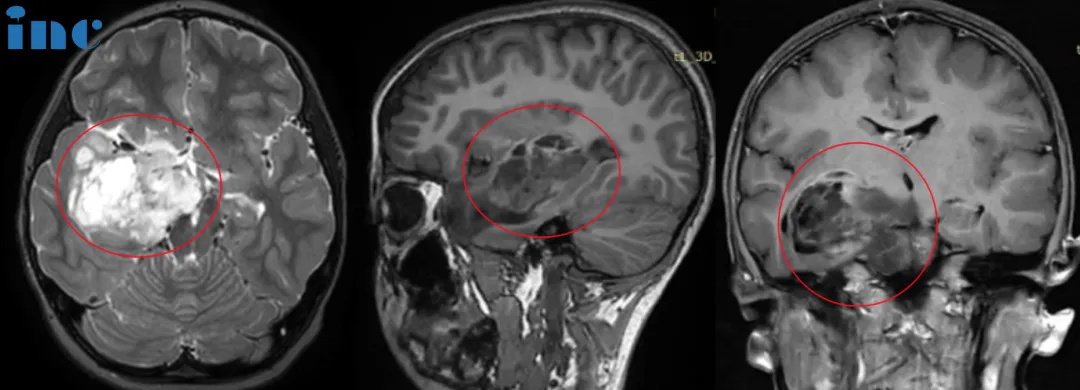

▼可可術(shù)前術(shù)后影像對(duì)比

可可術(shù)前術(shù)后影像對(duì)比

可可術(shù)后病理結(jié)果為WHO1級(jí)膠質(zhì)瘤,這代表著預(yù)后很好,可以長(zhǎng)期生存。術(shù)后1年,巴教授示范手術(shù)期間,我們?cè)俅我?jiàn)到了可可。她還是那么活潑可愛(ài),充滿活力。早已回到了校園的她,愛(ài)跳舞,和媽媽一起做瑜伽……術(shù)后隨訪的結(jié)果也令可可父母非常滿意。